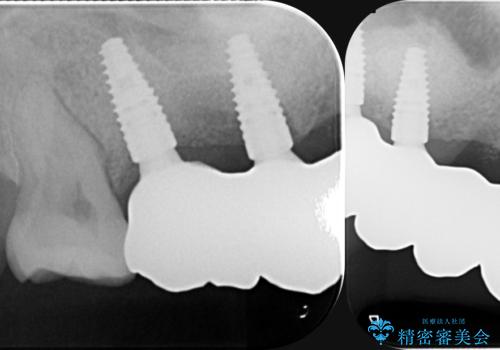

- 120万円(ストローマンインプラント×3・骨造成・チタンカスタムアバットメント×3・フルジルコニアクラウン×5)費用は治療当時の料金となります

連続した多数の歯の機能・審美回復にブリッジは設計上治療の手段になり得ない場合があります。

残された選択肢は入れ歯・インプラントになりますが審美性・咬合機能の回復度・快適さ・残存歯への負担は雲泥の差となります。